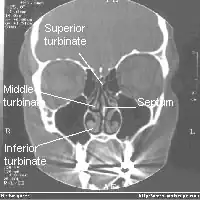

Il y a trois cornets dans chaque cavité nasale :

- le cornet inférieur : le plus grand, aussi long que l'index;

- le cornet moyen : aussi long qu'un auriculaire ;

- le cornet supérieur : très petit.

Les deux cavités nasales sont séparées par la cloison nasale appelée septum.